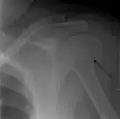

Fracture of the greater tuberosity of the humerus -

Multi-fragmented, or comminuted fracture of the proximal humerus with involvement of the greater tuberosity -